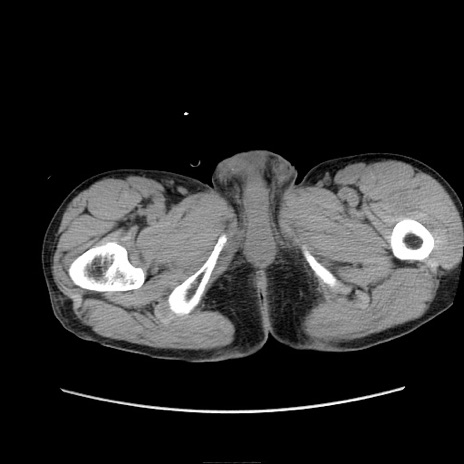

症例11(横断像)

【症例】 60歳代男性

【主訴】 下腹部痛

【現病歴】 本日夜中より下腹部痛の症状認め、受診。

【既往歴】 膀胱癌(膀胱全摘+尿管皮膚瘻術) 、胃癌術後

【身体所見】 BT 35.3℃、PR 58/min、BP 136/98mHg、腹部平坦、軟、腸蠕動音±、ストマ留置あり、左上腹部~正中部に圧痛あり、反跳痛なし。

【データ】WBC 5100、CRP0.01